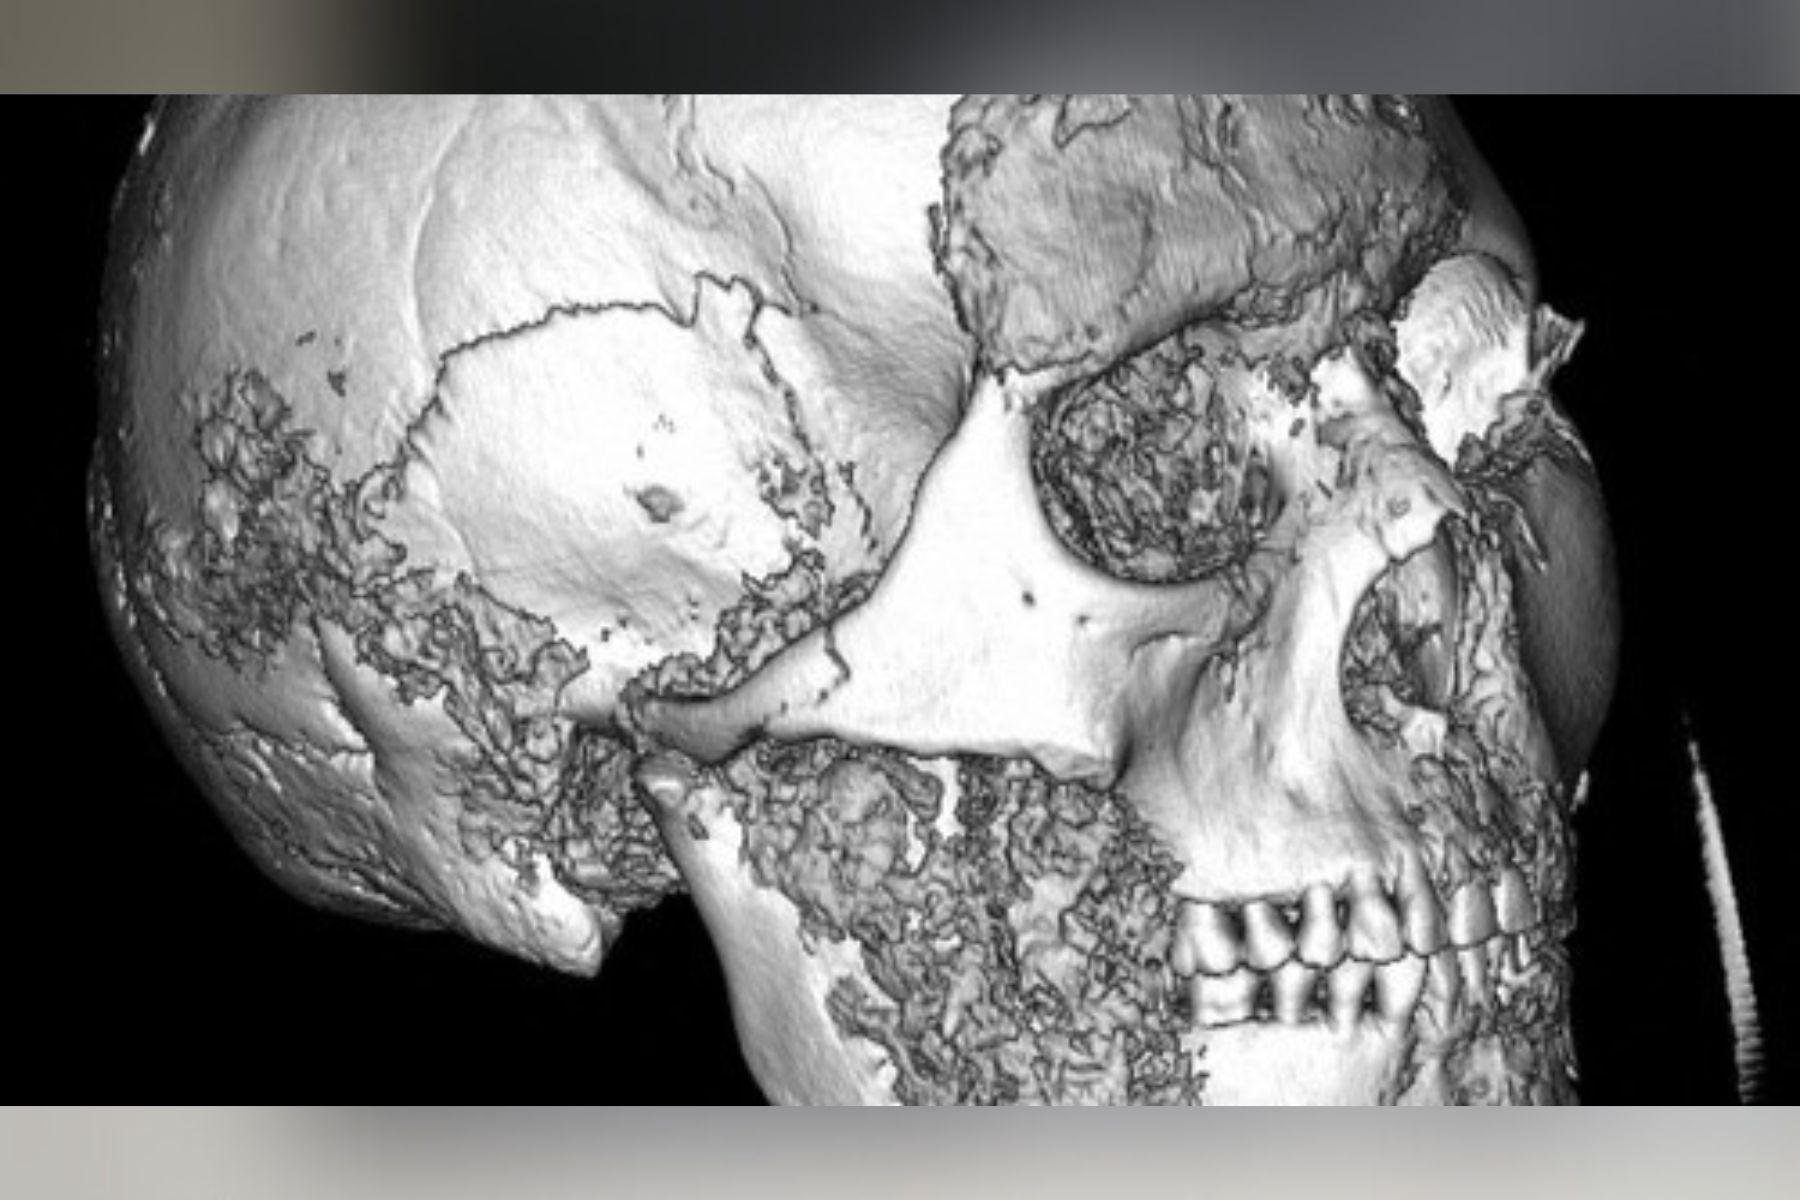

Raziskovalci lobanje zaradi stanja ohranjenega tkiva sprva niso mogli ustrezno pregledati, vendar so zdaj s pomočjo CT-slikanja ugotovili, da je ženska utrpela hudo poškodbo na desni strani lobanje, zaradi katere je imela uničen sklep, pretrgane podporne vezi in premaknjeno spodnjo čeljust.

Raziskovalci so obenem v čeljusti odkrili dva majhna izvrtana kanala, v katerih so našli sledi vsajenih materialov, ki najverjetneje pripadajo živalim. Po njihovih ocenah je to držalo čeljust skupaj in ženski omogočalo, da jo je sčasoma lahko spet uporabljala. Slike so pokazale tudi, da je okoli izvrtanih lukenj zrasla nova kost, kar kaže, da je ženska operacijo preživela.